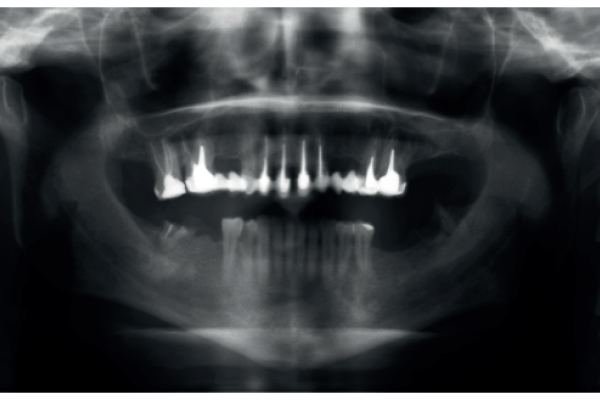

Injerto pediculado palatino en regeneración ósea guiada